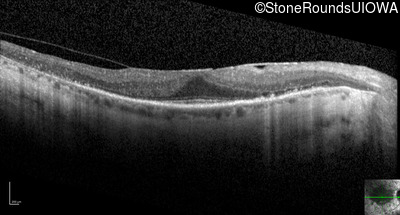

Optical Coherence Tomography - Left - 20/25 -2 sc

Exemplar / OCT Stack